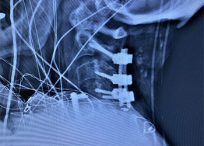

William J. Sonstein, M.D., F.A.C.S. is a Board-Certified Diplomate, American Board of Neurosurgery. He has a special interest in complex spine surgery and has one of the largest experiences with Posterior Lumbar Interbody Fusion (PLIF) on Long Island. This procedure relieves pain for patients with intractable back pain. Dr. Sonstein uses minimally invasive procedures whenever possible, such as Kyphoplasty and X-STOP™ to treat spinal compression fractures and spinal stenosis.

Case Studies